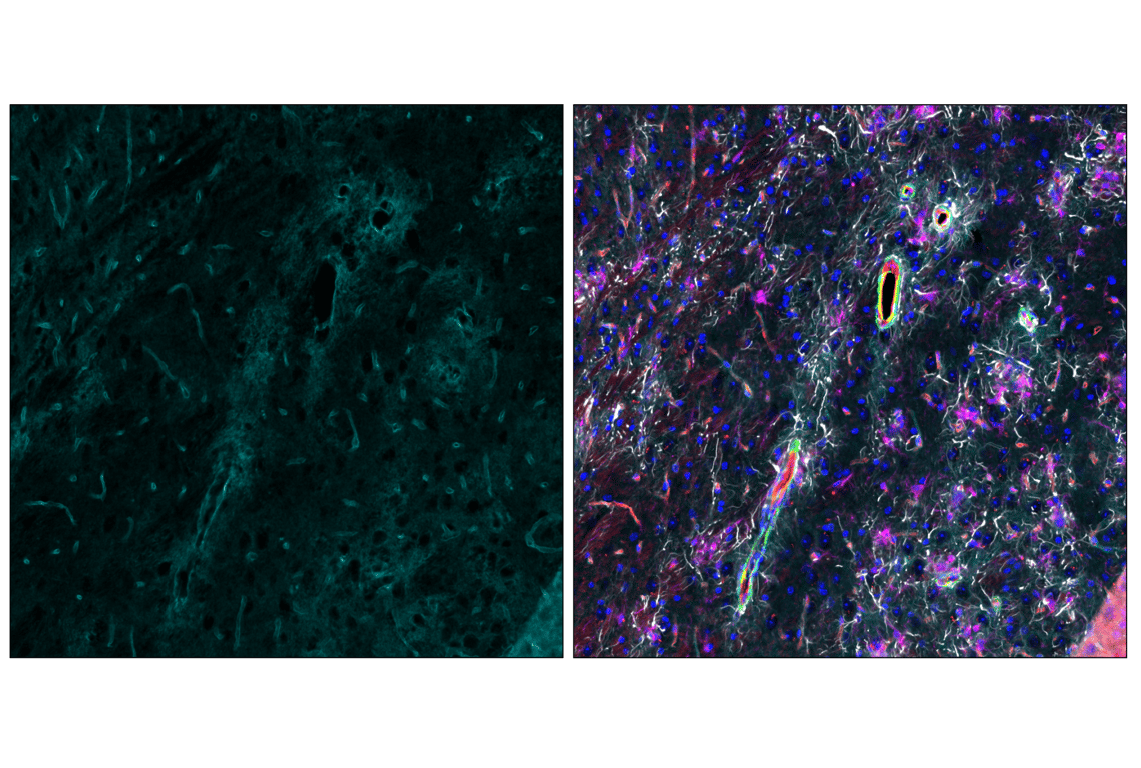

Cyclic multiplex immunofluorescent analysis of fixed frozen hippocampus from an amyloid mouse model of Alzheimer's Disease using CD31 (PECAM-1) (F2N3M) Rabbit mAb #15585 (red). After blocking free secondary antibody binding sites with Rabbit (DA1E) mAb IgG XP® Isotype Control #3900, the tissues were then labeled using α-Smooth Muscle Actin (1A4) Mouse mAb (Alexa Fluor® 488 Conjugate) #46469 (green) and  AQP4 (D1F8E) XP® Rabbit mAb (Alexa Fluor® 647 Conjugate) #89851 (cyan). Sections were mounted in ProLong Gold Antifade Reagent with DAPI #8961 (blue) and then imaged. After imaging, sections were processed in Western Blot Stripping Buffer (5X) #91925 to remove bound primary and secondary antibody. Then sections were labeled with GFAP (E4L7M) XP® Rabbit mAb (Alexa Fluor® 488 Conjugate) #94242 (gray) and Iba1/AIF-1 (E4O4W) XP® Rabbit mAb (Alexa Fluor® 647 Conjugate) #78060 (magenta). Sections were mounted in ProLong Gold Antifade Reagent with DAPI #8961 (blue) and then imaged a second time.

Immunofluorescence Image 5: AQP4 (D1F8E) Rabbit Monoclonal Antibody (Alexa Fluor<sup>®</sup> 647 Conjugate)